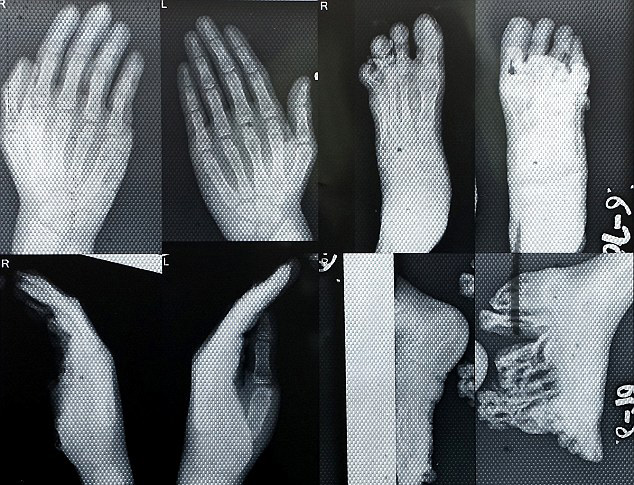

据英国《每日邮报》7月4日报道,印度三姐妹患有一种罕见的先天性皮肤病——奥姆斯特徳综合征,双脚脚掌不仅异常增厚,还长有肿瘤和溃疡。6月,在接受手术移除肿瘤后,三姐妹首次独立行走,目前恢复良好。

据报道,患病的三姐妹中,姐姐仅有12岁,还有一对8岁的双胞胎妹 妹。刚出生时,她们的双脚看上去并无异常。但到一周岁左右时,她们的脚底逐渐变厚,并伴有肿块增生。脚掌一旦落地,便会传来刺骨的疼痛,因此三姐妹无法正 常行走,她们的父母也饱受痛苦。在采访中,父亲阿比曼纽 塞蒂(Abhimanyu Sethi)说道:“我的女儿们无法像正常人一样生活。没人敢靠近她们,我们的邻居都不愿意和她们分享道具和餐盘,害怕被传染。这种疾病完全毁了我们的生活。”

而在6月,三姐妹终于看到了一线希望——当地的一家公立医院同意免 费为三姐妹进行手术治疗。医院整容外科的助理教授纳亚克博士对三姐妹进行了为期五天的细致诊察,才最终敲定手术治疗方案。纳亚克博士在采访中说道:“当 时,姐姐的病情已经十分严重,脚掌硬皮增生10英寸(约25厘米),如果情况继续恶化,她将面临截肢的风险。我从未见过这类病例,我们也针对这种病例制定 了全新的治疗方案。”

据悉,手术成功移除了三姐妹脚掌的肿瘤,术后一个月,三姐妹终于 踏出了独立行走的第一步。“双胞胎妹妹们已经能够自信行走,姐姐走路时仍有痛感,但是也会日渐好转。”纳亚克博士说道。她们的父母也对此欣喜万分。“看到 她们能够站起来,自己独立走路,我真的是太高兴了。”父亲塞蒂说道,“我希望有朝一日,能够送她们去上学。”